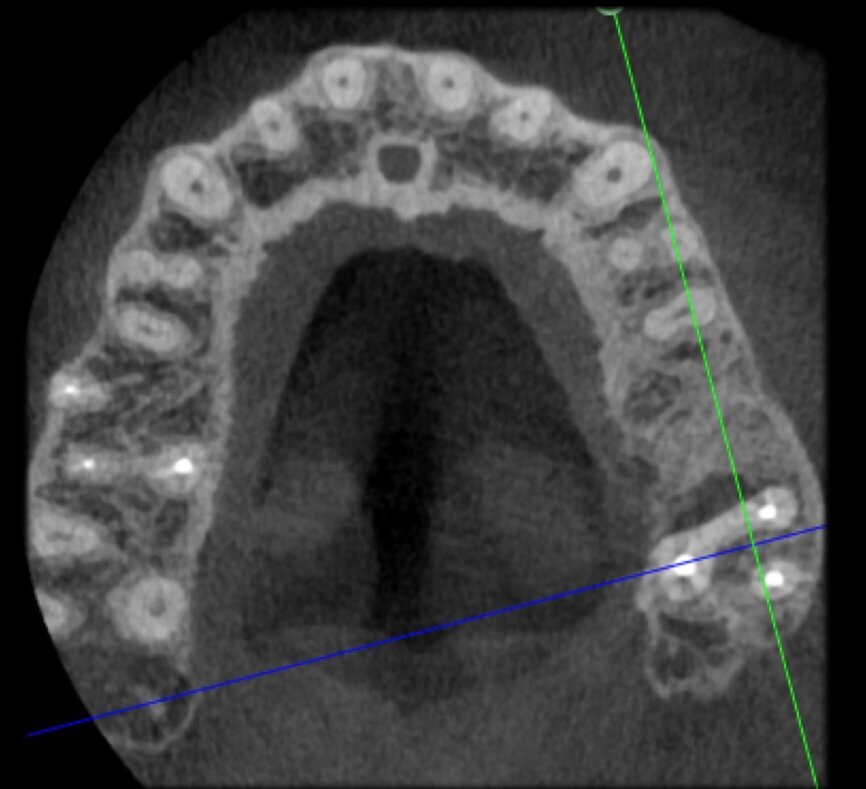

The case with which I would like to start my clinical review is a perfect example of how difficult it is to establish the origin of the patient’s symptoms on the basis of an intraoral radiograph alone. Not only does the 2D study fail to establish with certainty the presence of a lesion, but more importantly, it is impossible to establish the size, morphology and type of the lesion. An analysis of the 3D imaging, however, provides a clear picture of the clinical situation: the coronal and sagittal slices revealed the presence of a large lesion extending from the apex of the mesial root of this molar to the furcation, while the axial slices allow us to conduct a precise analysis of the endodontic anatomy and, in particular, the shape of the mesial root, which in this case was fused with the palatine root. A full overview of the case can, therefore, guide the decision-making process and direct the treatment plan towards a specific type of treatment (Figs. 1–4).